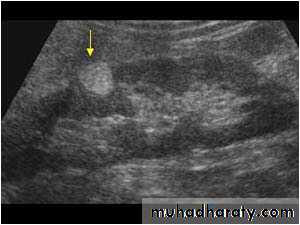

Simple cysts

Very common.

Filled with clear fluid(i.e anechoic).

Show obvious echoes from the front and back walls and posterior acoustic enhancement.

Most are spherical in shape.

Imperceptible walls

Solitary or multiple ,unilocular (simple)or have septations (not a simple cyst)

If contain low level echoes in dependent portion complicated by Hhg or infection.

No further investigations are needed.